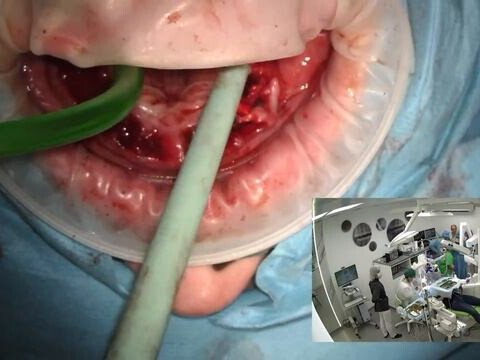

На базе медицинского центра открыто отделение челюстно-лицевой хирургии. Также мы сможем помочь с.

Смык Александр Александрович работает в сфере стоматологической хирургии. Помощь стоматолога-хирурга может потребоваться не только при необходимости удалить зуб, который невозможно восстановить. Александр Смык также производит лечение воспалительных болезней полости рта, удаление новообразований и даже эстетическая пластика десен.

Удаление зубов любой сложности

Имплантация любой сложности

Имплантация по системе All-on-4/6

Синус-лифтинг

Костные пластики

Пластика мягких тканей

Скрипко Валерий Игоревич работает в сфере имплантологии, стоматологической и челюстно-лицевой хирургии.

Почикян Самвел Араратович работает в сфере имплантологии и стоматологической хирургии. К нему обращаются, когда возникает необходимость реконструировать целостность зубных рядов, сделать улыбку сияющей и получить шанс вновь полноценно пережевывать еду. Самвел Почикян также может подобрать зубные импланты и грамотно организовать все сопутствующие процедуры по подготовке и вживлению импланта.